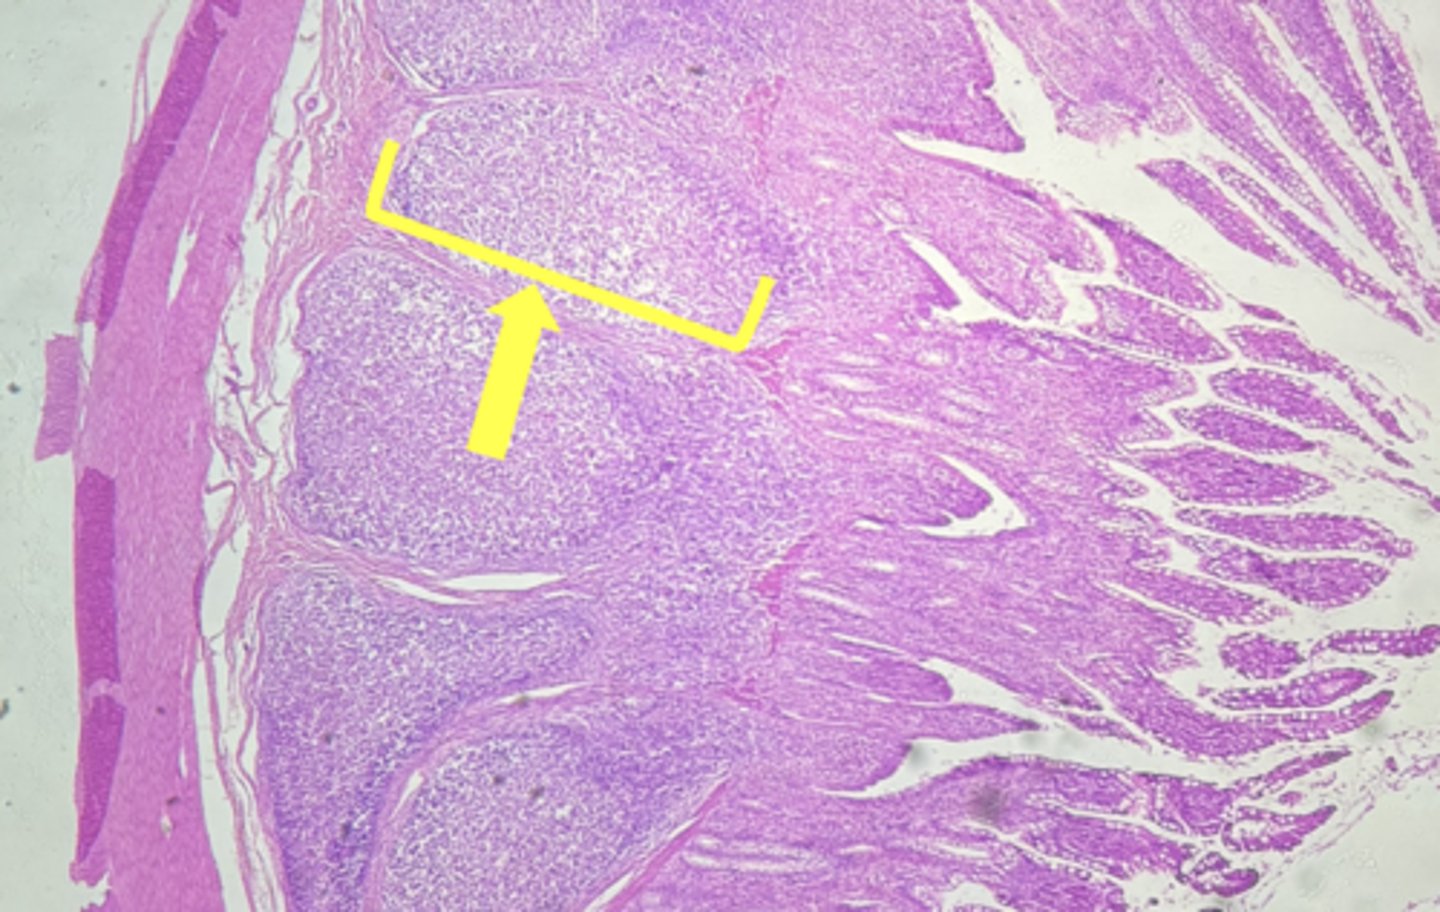

Esophagus

name the tissue

Mucosa

(esophagus)

Submucosa

muscularis externa

stratified squamous epithilium (KEY CHARACTERISTIC)

lamina propria

muscularis mucosae

circular layer

longitudinal layer

A- Esophagus

B- Stomach

Name the Tissue A & B